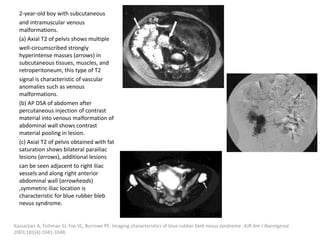

can then be treated with the sclerosant.

Müller-Wille R, Wildgruber M, Sadick M, Wohlgemuth WA. Vascular Anomalies (Part II): Interventional Therapy of Peripheral Vascular

Malformations [published online ahead of print, 2018 Feb 7]. Gefäßanomalien (Teil II): Interventionelle Therapie von peripheren

Gefäßmalformationen [published online ahead of print, 2018 Feb 7]. Rofo. 2018;10.1055/s-0044-101266.

Post-procedural care

Strict postoperative observation of the upper

airway is recommended after treatment of

patients with large cervical LMs.

Fever after injection of Picibanil can be treated

with paracetamol.